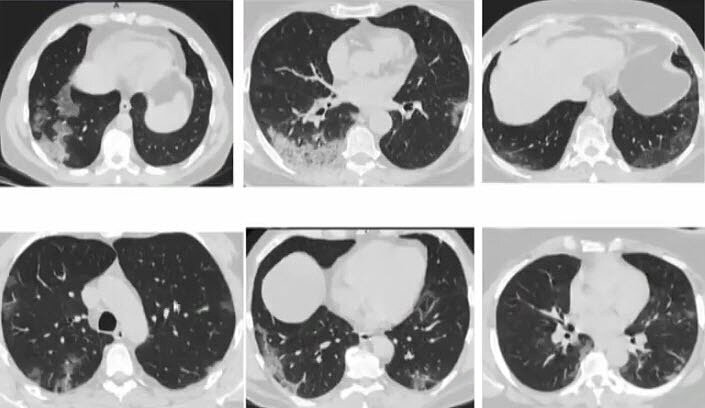

2 кт подряд

2 кт подряд 111 фото